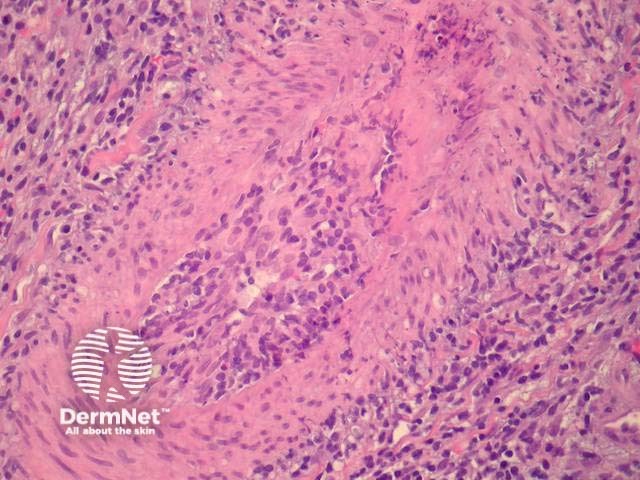

Histological features of systemic and localised cutaneous forms of polyarteritis nodosa are similar. A deep biopsy is preferred as cutaneous polyarteritis nodosa involves medium-sized vessels in the deep dermis and subcutis (Figure 1). Early lesions show fibrinoid necrosis with thickening and infiltration of the vessel wall. Neutrophils, eosinophils and lymphocytes are present (Figures 2,3). Leucocytoclasis may be present. Thrombi and aneurysmal change may occur and lead to necrosis of the overlying epithelium. In mature lesions vessel occlusion occurs secondary to intimal and mural fibrosis. Lesions at various stages are characteristic and changes are discontinuous with uninvolved skip lesions between affected segments.

Figure 2

Figure 3